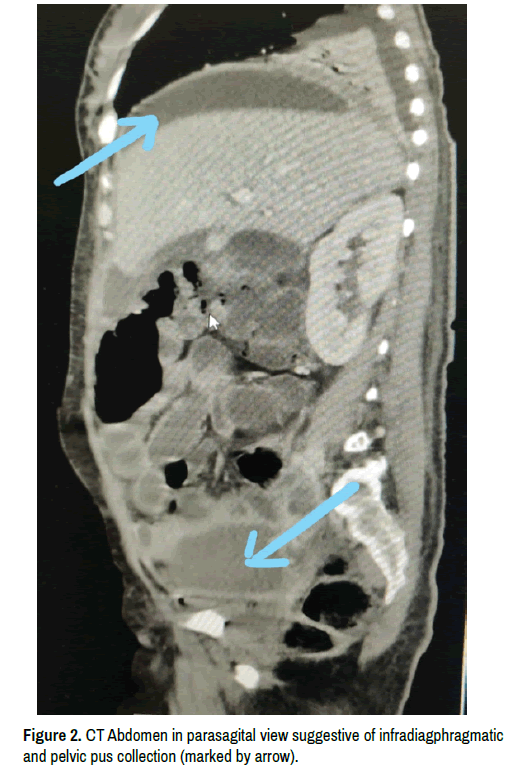

Primary care physicians should be aware about the possibility of primary peritonitis in young adults (females predominantly) and its relatively simplistic management algorithm for favorable outcomes, if instituted timely (Figure 1 & Figure 2).

clinical-infectious-diseases-suggestive

Figure 2. CT Abdomen in parasagital view suggestive of infradiagphragmatic and pelvic pus collection (marked by arrow).